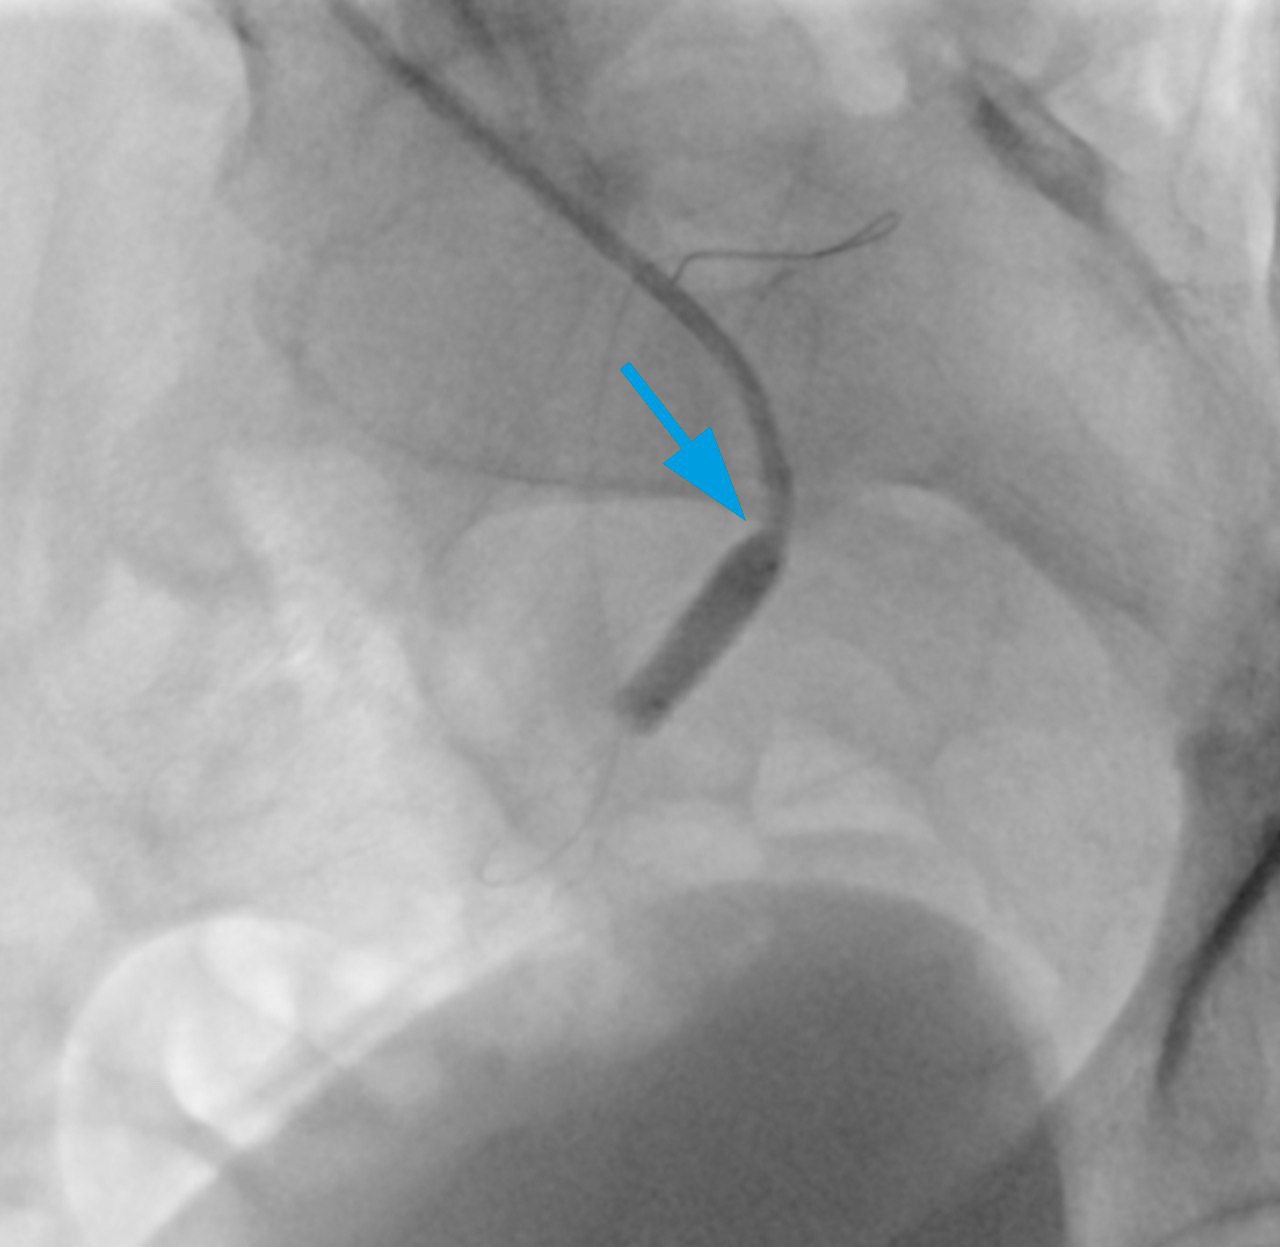

Однако с заведением стента в место стеноза возникли сложности. С целью их разрешения была использована техника с глубокой интубацией почечной артерии. Это позволило успешно доставить и имплантировать стент в почечную артерию трансплантата (рис. 2).